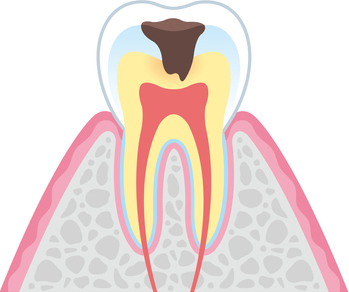

虫歯の進行段階

- C1

エナメル質の虫歯

歯の表面のエナメル質が溶かされ、虫歯が少しずつ進行している状態です。虫歯を正確に削り取り、詰め物をするケースがほとんどです。削らずに定期的なチェックを行うこともあります。

- C2

象牙質の虫歯

エナメル質の奥の象牙質にまで細菌が進行している状態です。象牙質は神経に近いため、知覚過敏として歯がしみるようになります。虫歯を削り取り、詰め物や被せ物をするのが基本です。

- C3

神経まで侵された虫歯

歯の神経が虫歯菌に感染し、強烈な痛みを引き起こします。細菌に感染した組織を除去・清掃・殺菌し、被せ物を被せていきます。

- C4

歯の根まで達した虫歯

歯の大部分が失われている状態です。根の先端に膿が溜まっていると、顎の骨や周囲の歯に悪影響を及ぼすようになり非常に危険です。多くのケースで抜歯を検討します。